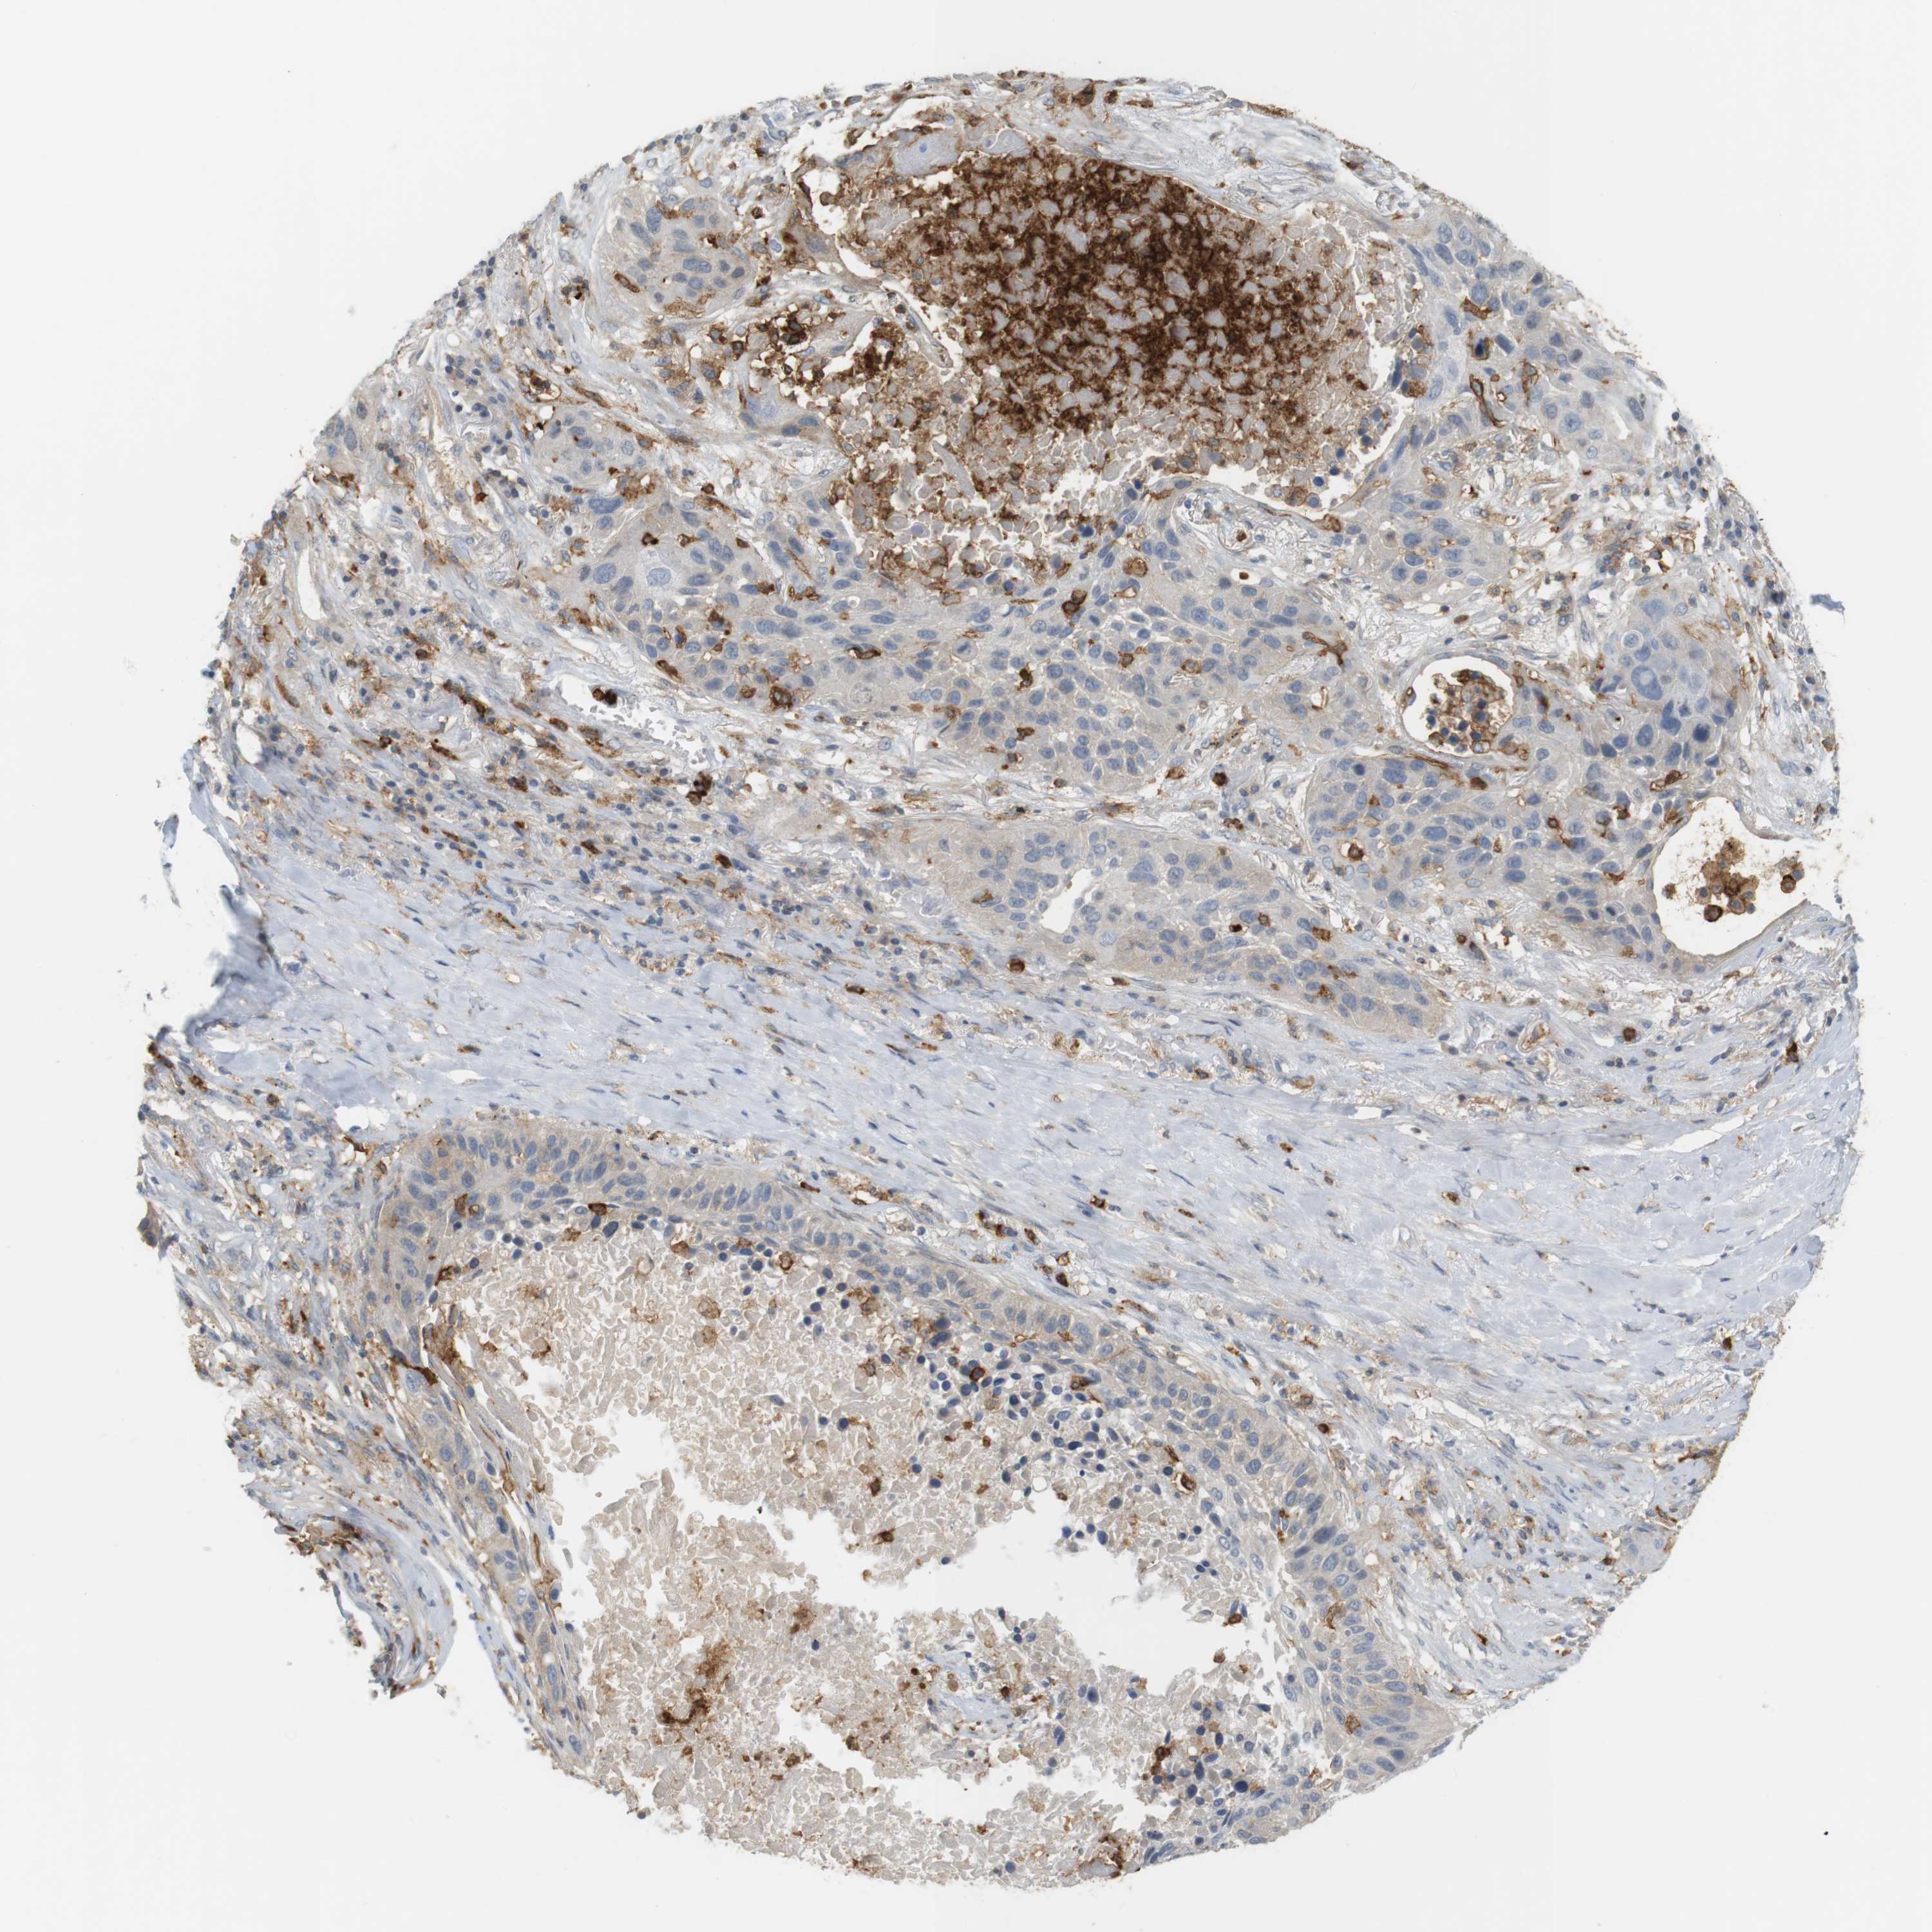

CANCER LUNG CANCER Show tissue menu

LUAD TCGA LUAD VALIDATION LUSC TCGA LUSC VALIDATION PROTEIN LUAD CPTAC PROTEIN LUSC CPTAC PROTEIN EXPRESSION